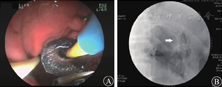

2019年11月26日患者再次出现发热,体温最高达39.6 ℃,伴畏寒、寒战,血压下降,最低血压为76/50 mmHg,药敏试验结果示广泛耐药的肺炎克雷伯杆菌、屎肠球菌和嗜麦芽窄食单胞菌感染,调整抗生素为利奈唑胺(0.6 g/次,2次/d)联合替加环素(50 mg/次,2次/d)抗感染治疗,并予血浆1 000 mL扩容补液,去甲肾上腺素(4 mg/次,2 mL/h)和多巴胺(180 mg/次,10 μg·kg-1·min-1)升压治疗,患者血压恢复至123/80 mmHg。经多学科会诊后考虑胰周假性囊肿出血后合并感染,治疗仍以抗感染和胰周引流为主,调整抗生素为头孢他啶阿维巴坦钠(2.5 g/次,3次/d)和利奈唑胺(0.6 g/次,2次/d),2019年12月2日腹部CT检查示胰周积液和胰周脓肿腔仍存在(图5A),并于2019年12月9日在X线引导下循胃体后壁窦道处,置入双猪尾长7 cm、直径7 F的塑料支架,支架置入后胃腔可见胰周脓液溢出,后患者体温逐渐下降,12月13日CT检查示胰周积液和胰周脓肿腔逐渐缩小(图5B)。患者于2020年1月13日腹部CT检查示胆总管下段轻度扩张,胆总管下段结石,于1月19日行内镜逆行胰胆管造影术(endoscopic retrograde cholangiopancreatography,ERCP)、胆管支架置术和胰管支架置入术(图6),术后逐渐开放饮食并于2020年1月23日出院。2020年3月26日拔除胃内支架和胆胰管支架,至截稿患者病情稳定。

单猪尾支架怎么放重症急性胰腺炎合并出血性休克和感染性休克_https://www.jmylbn.com_新闻资讯_第7张

图6 2020年1月19日行内镜逆行胰胆管造影术

A 放置胆胰管双支架 B 经胃囊肿引流支架(红色箭头所示)、胆管支架(白色箭头所示)和胰管支架(蓝色箭头所示)定位